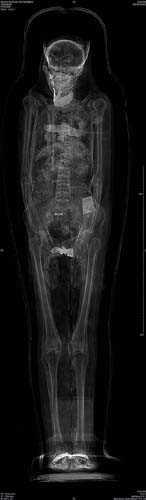

2. Fotoğrafta gördüğünüz Mısır mumyasının CT taraması, uygarlığının gizemlerini çözmeye yardımcı olacak.

Fotoğrafta gördüğünüz Mısır mumyasının CT taraması, uygarlığının gizemlerini çözmeye yardımcı olacak.

4. Dr. Helmi, British Museum'dan özel izinle aldığı yedi mumya üzerinde bu cihazı test etti.

Dr. Helmi, British Museum'dan özel izinle aldığı yedi mumya üzerinde bu cihazı test etti.

5. Yapılan taramalar M.Ö. 900 civarında Mısırlıların sağlığı ve davranışları konusunda önemli ipuçları verdi.

Yapılan taramalar M.Ö. 900 civarında Mısırlıların sağlığı ve davranışları konusunda önemli ipuçları verdi.